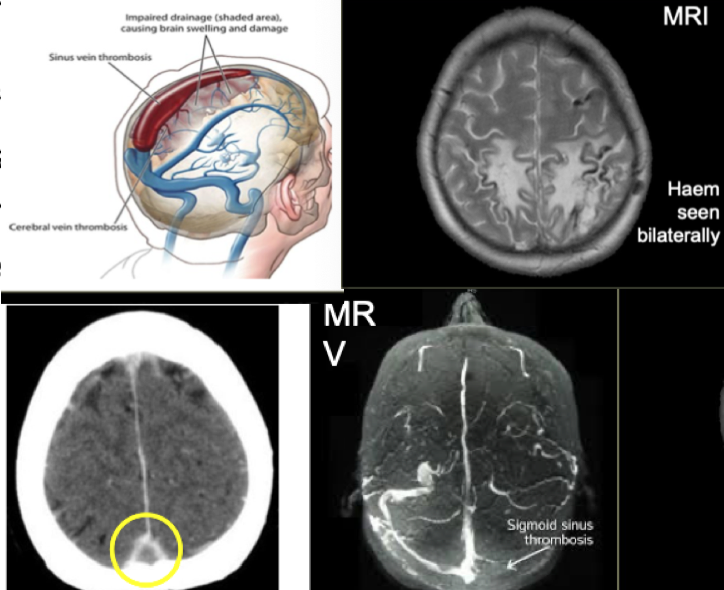

What are the features of cerebral venous sinus thrombosis ?

A

Presentation & referral;

- Often female, on oral contraceptive pill

- Headache, often severe

- Raised intracranial pressure

- Often papilloedema and seizures

- Maybe MR bilateral, haemorrhage and

- empty delta sign

- Refer on to neurosurgical centre